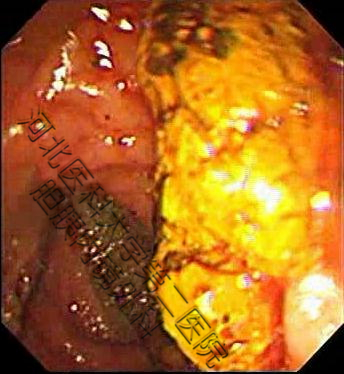

生活中并不缺少美,而是缺少发现美得眼睛,结石虽万恶,但具“自身美”,内镜下的结石也是“横看成岭侧成峰,奇形怪状各不同。簇拥颗粒如桑葚,表面圆滑似卵石。大如蜜枣小如豆,黑黄可见多半棕......”。接下来我们来一起欣赏百张内镜下取石的图片。(所见结石均已从胆总管取出,放入肠道内随大便排出)